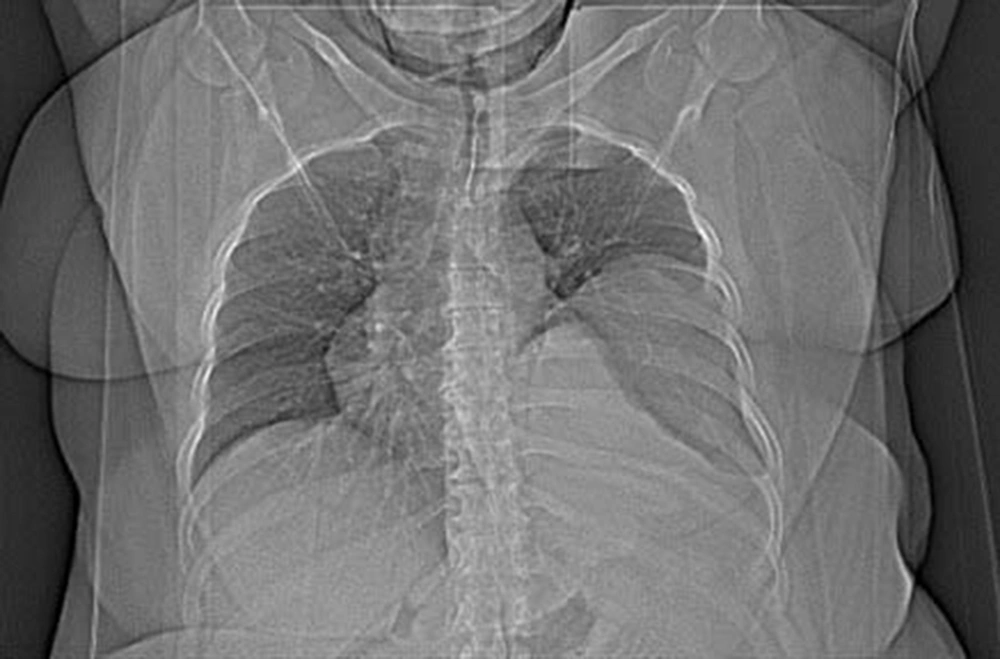

The patient was a 42 year old woman with pulmonary hydatid cyst who was admitted for left thoracotomy. She weighed about 110 kg and her body mass index (BMI) was about 42 kg/m2. She had a history of asthma since two years ago which was under treatment by inhaled Salbutamol and Seretide (PRN). In chest CT scan a large thick walled homogenous cystic lesion (12 cm, 5.8 cm, 8 cm) was seen in the left lower hemi-thorax (Figures 1 and 2).